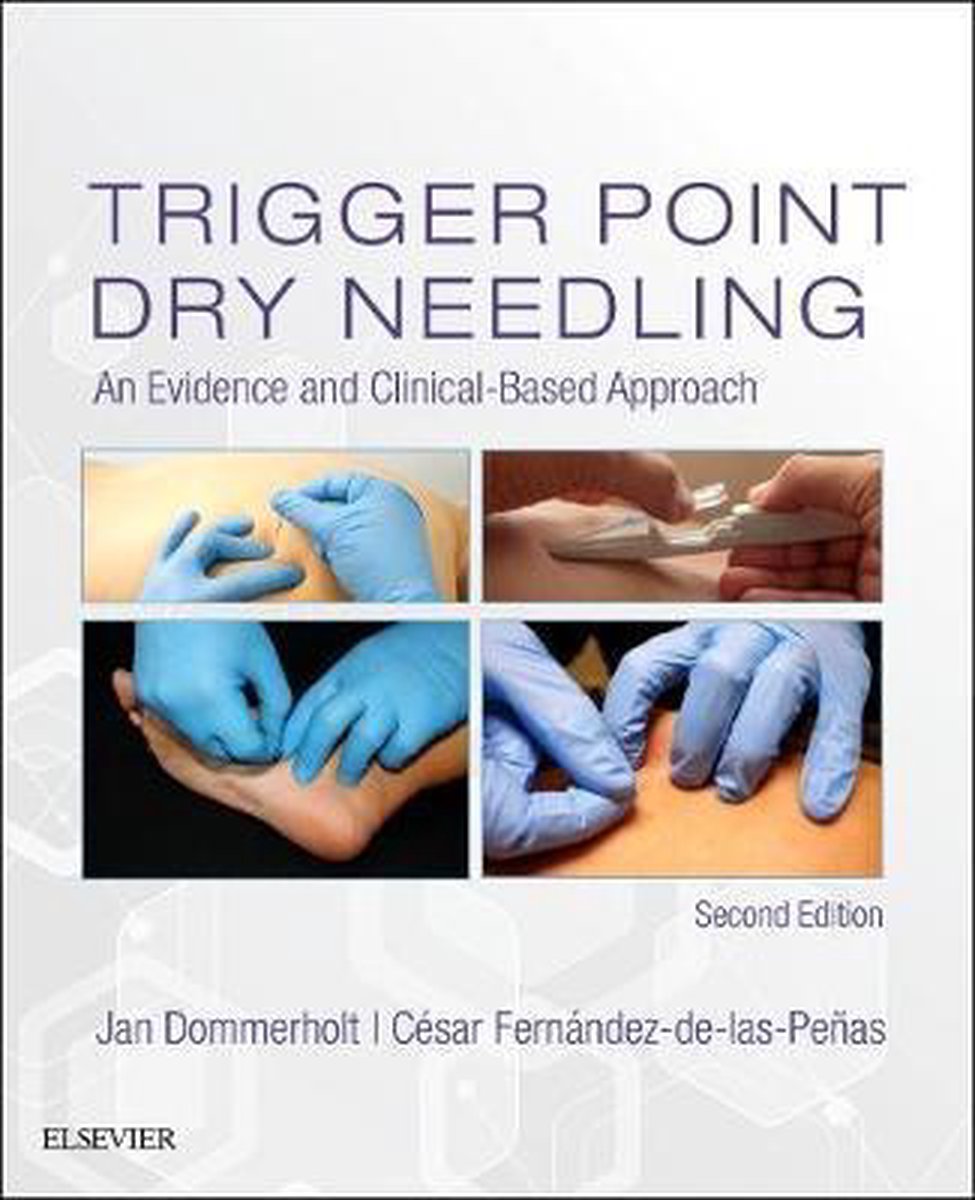

bol.com | Trigger Point Dry Needling | 9780702074165 | Jan Dommerholt …

Dry Needling for Manual Therapists points, Techniques and Treatments …

Dry Needling formation | Livre puncture kinésithérapique